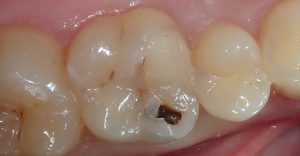

récidive de carie sous une résine ancienne

carie vue grâce au « carie detector »